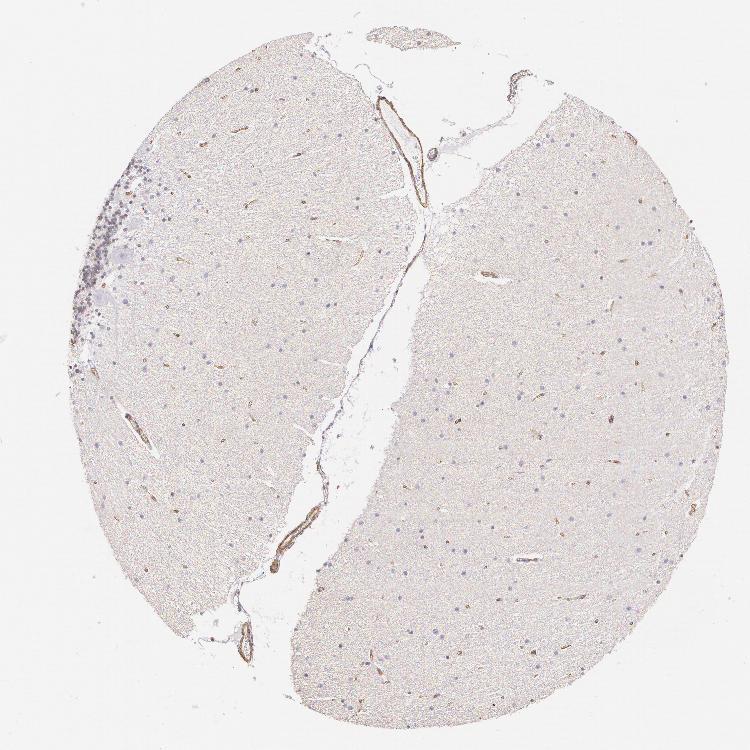

CEREBELLUM - Antibody stainingi

Antibody staining in the annotated cell types in the current human tissue is reported as not detected, low, medium, or high, based on conventional immunohistochemistry profiling in selected tissues. This score is based on the combination of the staining intensity and fraction of stained cells.

Each image is clickable and will lead to virtual microscopy that enables deeper exploration of all samples and also displays staining intensity scores, fraction scores and subcellular localization as well as patient and tissue information for each sample.

Antibody CAB002779Antibody CAB016119

Purkinje cells Not detectedNot detected

Cells in granular layer Not detectedHigh

Cells in molecular layer Not detectedNot detected